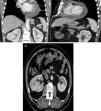

Thoracic-abdominal-pelvic computed tomography (CT) was performed to characterize the pericardial effusion and cardiac mass and to exclude associated cancer. This confirmed a lesion with contrast uptake in the vicinity of the right atrium (Figure 3A), together with a solid, nodular lesion in the right kidney suggestive of RCC (Figure 3B). Cardiac and abdominal magnetic resonance imaging (MRI) was also performed, which was inconclusive as to whether the cardiac lesion was primary or secondary but which confirmed the suspicion of primary renal cancer.